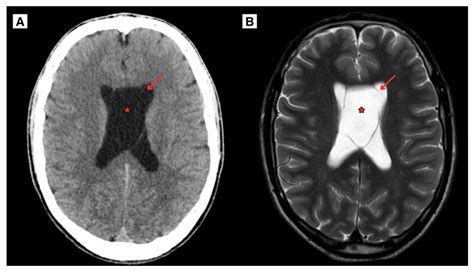

Diagnostic Imaging of the Cavum Septum Pellucidum

Diagnostic imaging techniques, such as magnetic resonance imaging (MRI), are essential for visualizing the Cavum Septum Pellucidum and assessing its size and shape. MRI provides high-resolution images of the brain, allowing clinicians to detect abnormalities in the Cavum Septum Pellucidum and other structures.

| Computed Tomography (CT) | Uses X-rays to create cross-sectional images of the brain | Less commonly used for Cavum Septum Pellucidum assessment |

MRI is the preferred imaging technique for evaluating the Cavum Septum Pellucidum due to its high resolution and ability to differentiate between soft tissues. CT scans and PET scans may also be used in specific clinical contexts, but they are less commonly employed for assessing the Cavum Septum Pellucidum.